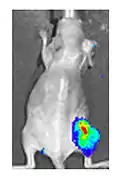

Both in the laboratory and in the clinic it is useful to have a simple means of identifying cells infected by the experimental virus. This can be done by equipping the virus with "reporter genes" not normally present in viral genomes, which encode easily identifiable protein markers. One example of such proteins is GFP (green fluorescent protein) which, when present in infected cells, will cause a fluorescent green light to be emitted when stimulated by blue light.[87][88] An advantage of this method is that it can be used on live cells and in patients with superficial infected lesions, it enables rapid non-invasive confirmation of viral infection.[89] Another example of a visual marker useful in living cells is luciferase, an enzyme from the firefly which in the presence of luciferin, emits light detectable by specialized cameras.[87]

- Yu YA, Shabahang S, Timiryasova TM, Zhang Q, Beltz R, Gentschev I, Goebel W, Szalay AA (March 2004). "Visualization of tumors and metastases in live animals with bacteria and vaccinia virus encoding light-emitting proteins". Nature Biotechnology. 22 (3): 313–20. doi:10.1038/nbt937. PMID 14990953. S2CID 1063835.